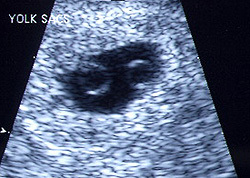

توأمان في الاسبوع الخامس

يبدأ الجنين في الأسبوع الخامس في بداية تكوينه ويسمى في هذه الفترة وحتى 3 شهور (حميل) والحميل هو الجنين منذ بداية تلقيح البويضة وحتى الأسبوع 12. فهو الآن ينمو داخل الرحم. وينقسم إلي ثلاث طبقات تكون كل طبقة منهم الأعضاء والأنسجة فيما بعد. وفي مؤخرة الرأس لأسفل، هناك طبقتين نسيج تكون الأذن بعد ذلك.